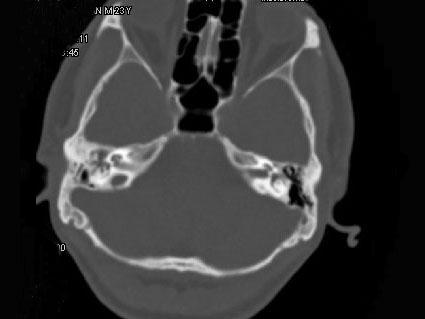

问题 男,23岁,右耳流脓十余年,右外耳道流脓,鼓膜穿孔,CT检查如图,最可能诊断为 ( )

选项 A、嗜酸性肉芽肿 B、(海绵化期)耳硬化症 C、中耳乳突结核 D、中耳癌 E、慢性中耳乳突炎

答案 E